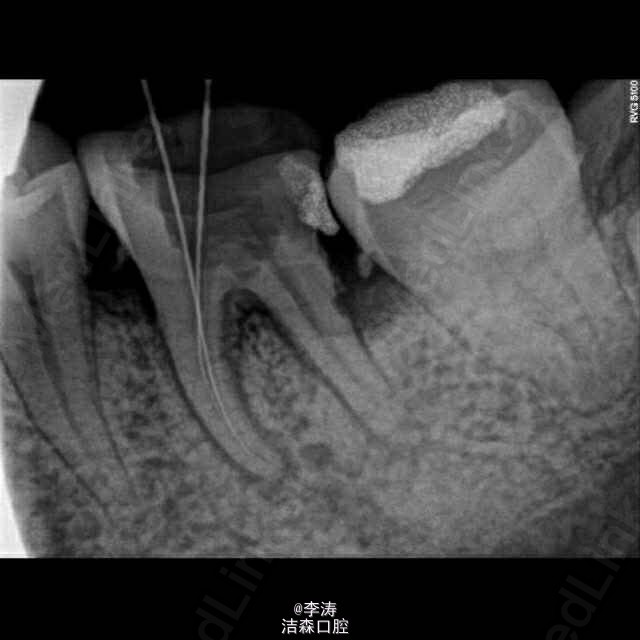

根管预备形成台阶1例

36牙根管治疗,近中根略弯曲,先疏通至15号,k3冠向下法预备,预备时形成台阶,然后怎么预弯都下不去! 太弯根管的还是应该使用手扩,特别是k3,弯曲根管尽量不用,容易形成台阶。另外预备过程中不能使用暴力!!